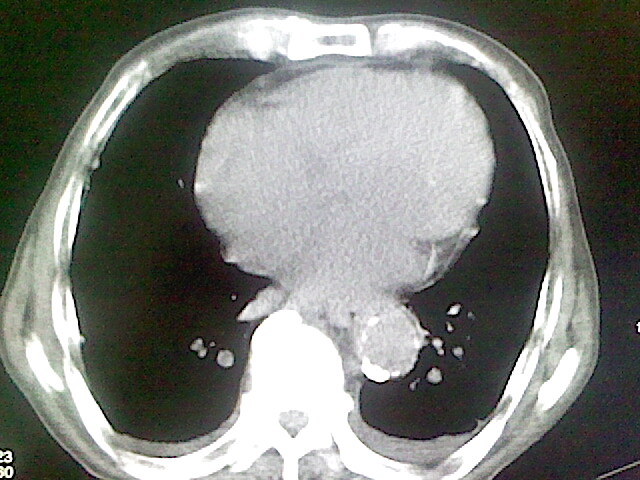

以下是引用zsl6918在2008-8-28 16:49:00的发言:[br]双肺炎性病灶,食管狭窄估计与心房增大压迫所致。

以下是引用xulianj在2008-8-28 20:36:00的发言:[br]慢支肺气肿伴感染,右上肺陈旧性结核;食道建议胃镜检查。

以下是引用wqs571018在2008-8-28 21:18:00的发言:[br]慢支继发感染,右上肺陈旧性结核;食道建议胃镜检查。